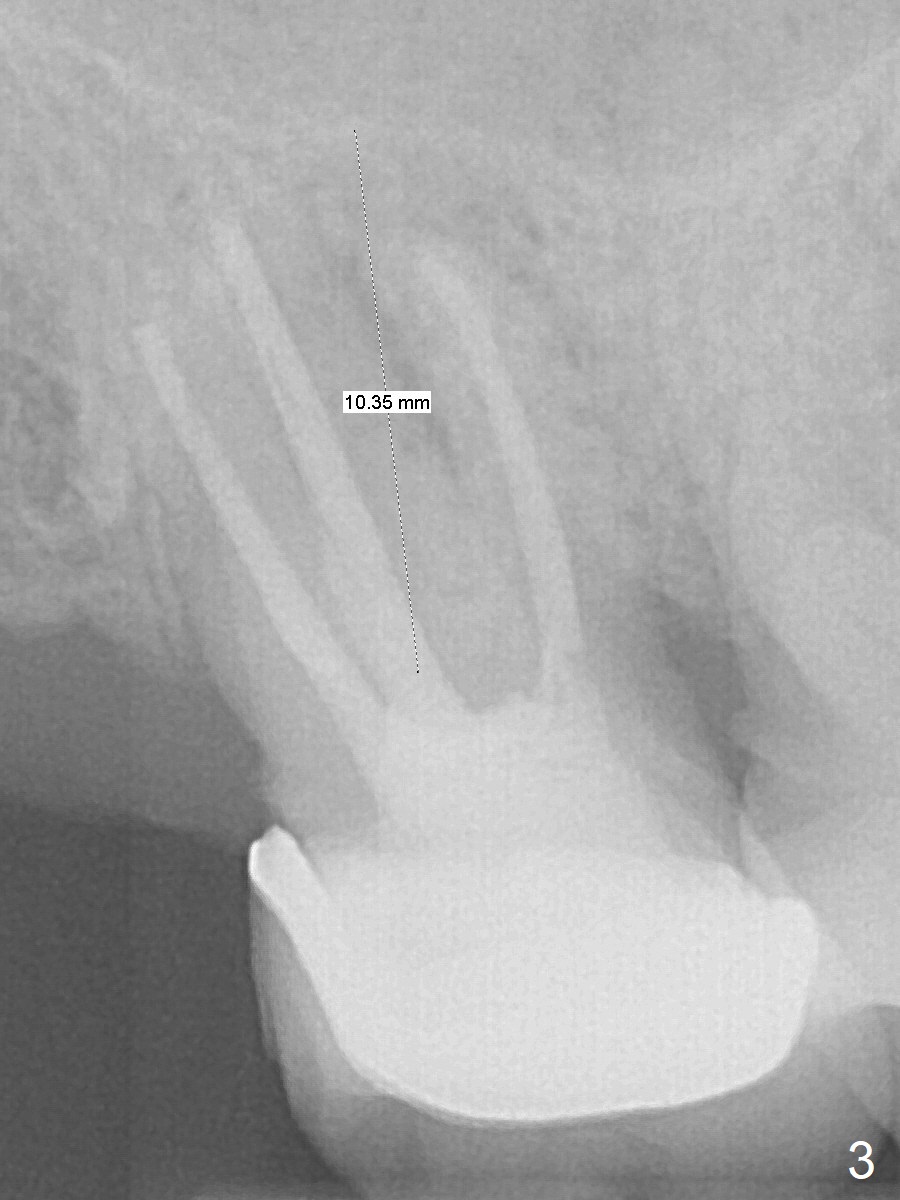

A 65-year-old man returned to finish LR and LL quadrant SRP a few weeks post SRP for UR quadrant and #2 extraction (Fig.1-2). He returns for UL SRP tomorrow ~ 3 months post extraction (Fig.4). Although the patient cannot remember whether socket preservation is done or not, there appears to be bone graft in the socket. The ridge is wide. It seems reasonable to expand and condense the socket using Magic Split and Expanders (flapless). If the patient cannot tolerate tapping, use DIO Bone Expanders. A 6.5x9 (3) mm Magicore will be placed (Fig.5,6).